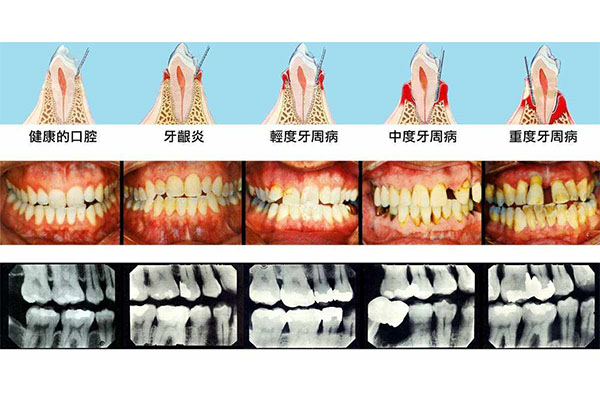

发生牙龈炎以后,建议进行洁牙的处理,通过超声波洁治器械对牙面上牙龈缘附近的菌斑和牙石进行清洁。同时术后应配合使用淡盐水进行漱口,保持口腔卫生,通常一周或者是两周左右可以消除。牙龈炎是常见的牙周组织疾病,是指牙龈组织发炎。正常情况下,牙龈是粉红色,菲薄而紧贴于牙面,发生牙龈炎以后,会有刷牙出血、口腔异味等情况出现。牙龈炎发生的常见原因是局部菌斑和牙石的刺激。而菌斑和牙石是不断形成,所以牙龈炎并不能一次性治愈,往往需要半年到一年进行一次牙石的清除,从而可以达到维护牙龈组织的健康程度。